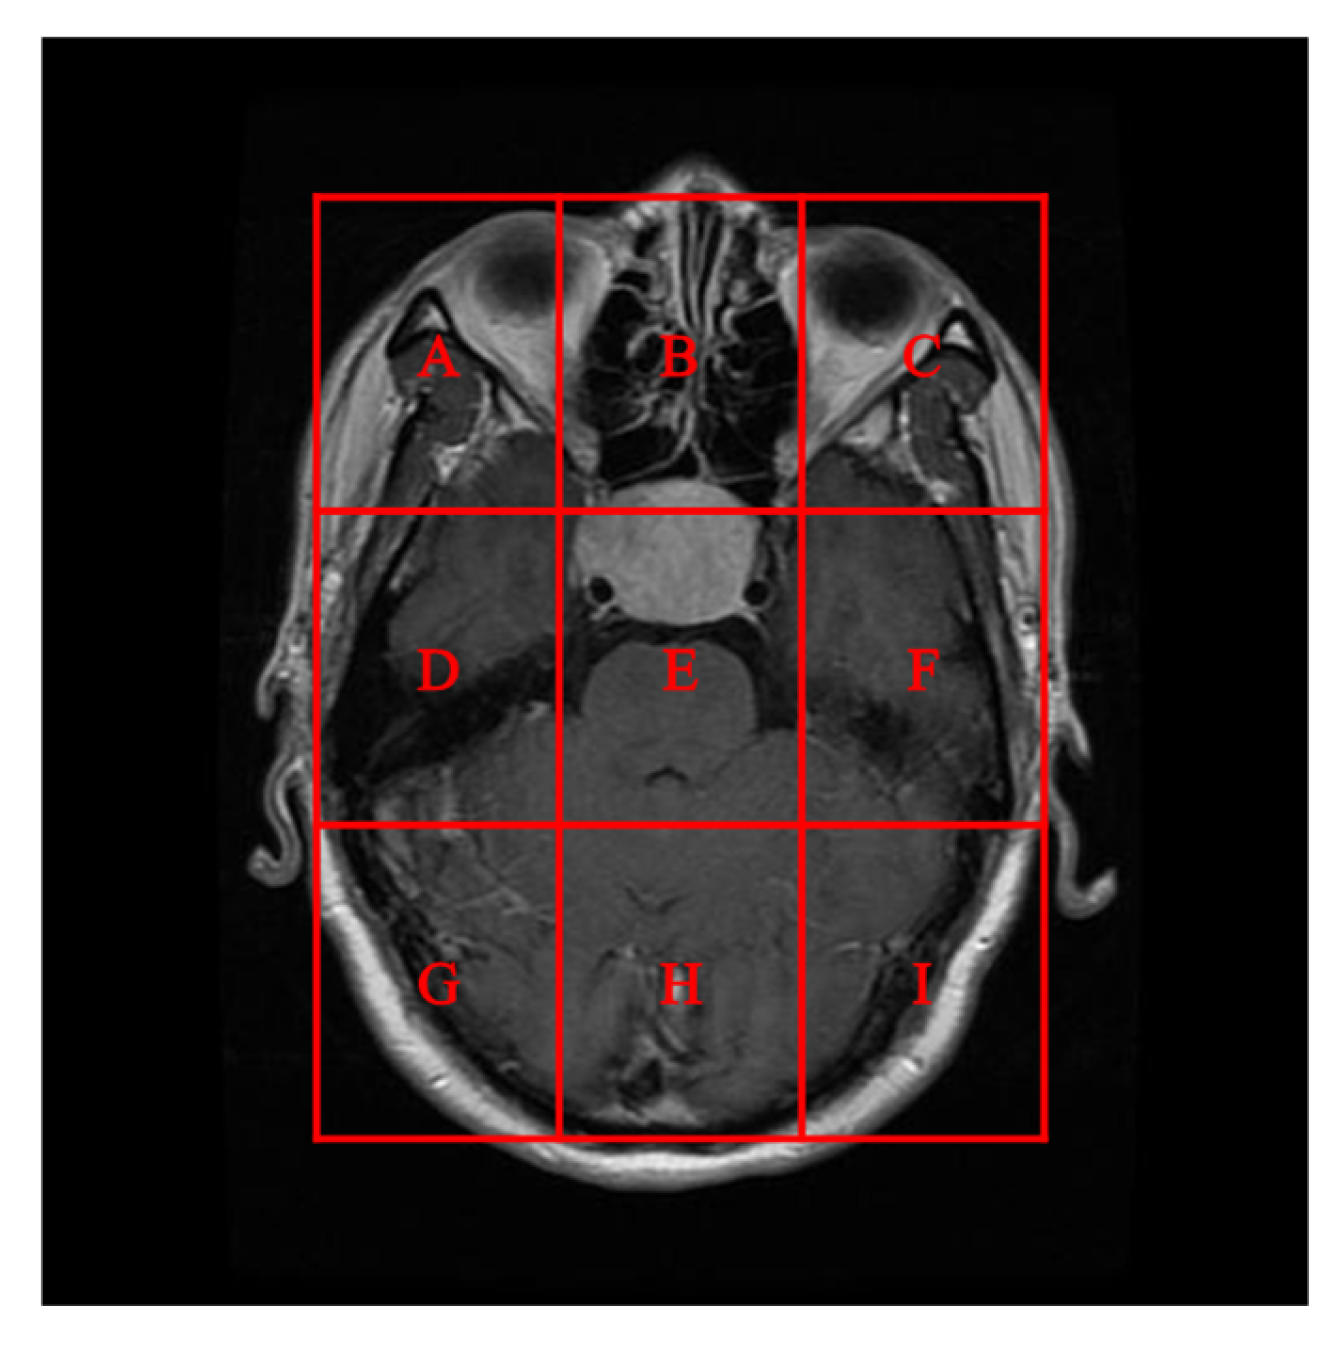

To better align our VUF-MIWS with the practical needs of clinicians for authenticating medical image sources, we conducted a pilot interview at a regional hospital. In this interview, we defined the critical diagnostic reference area of a medical image as the ROI (Region of Interest) and divided it into nine sub-regions, as shown in Figure 14. We then asked seven doctors to indicate their two most preferred locations for visible watermarks. Based on the collected feedback, sub-region A received the highest number of votes (a total of nine), followed by sub-regions E and I (both receiving five votes). Therefore, sub-region A was selected as the watermark position for the first and second experiments. The resulting watermarked images for the first experiments are displayed in Figure 15.

Figure 14.

In the first and second experiments, nine sub-regions were designated as position candidates for the visible watermark.